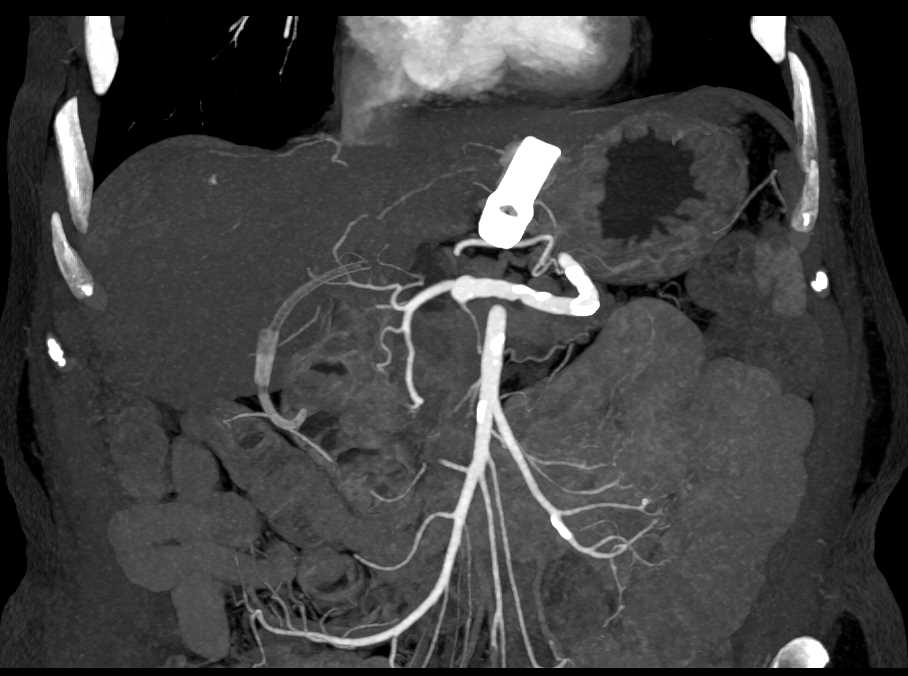

Gastroduodenal Artery (GDA) on MIP Imaging